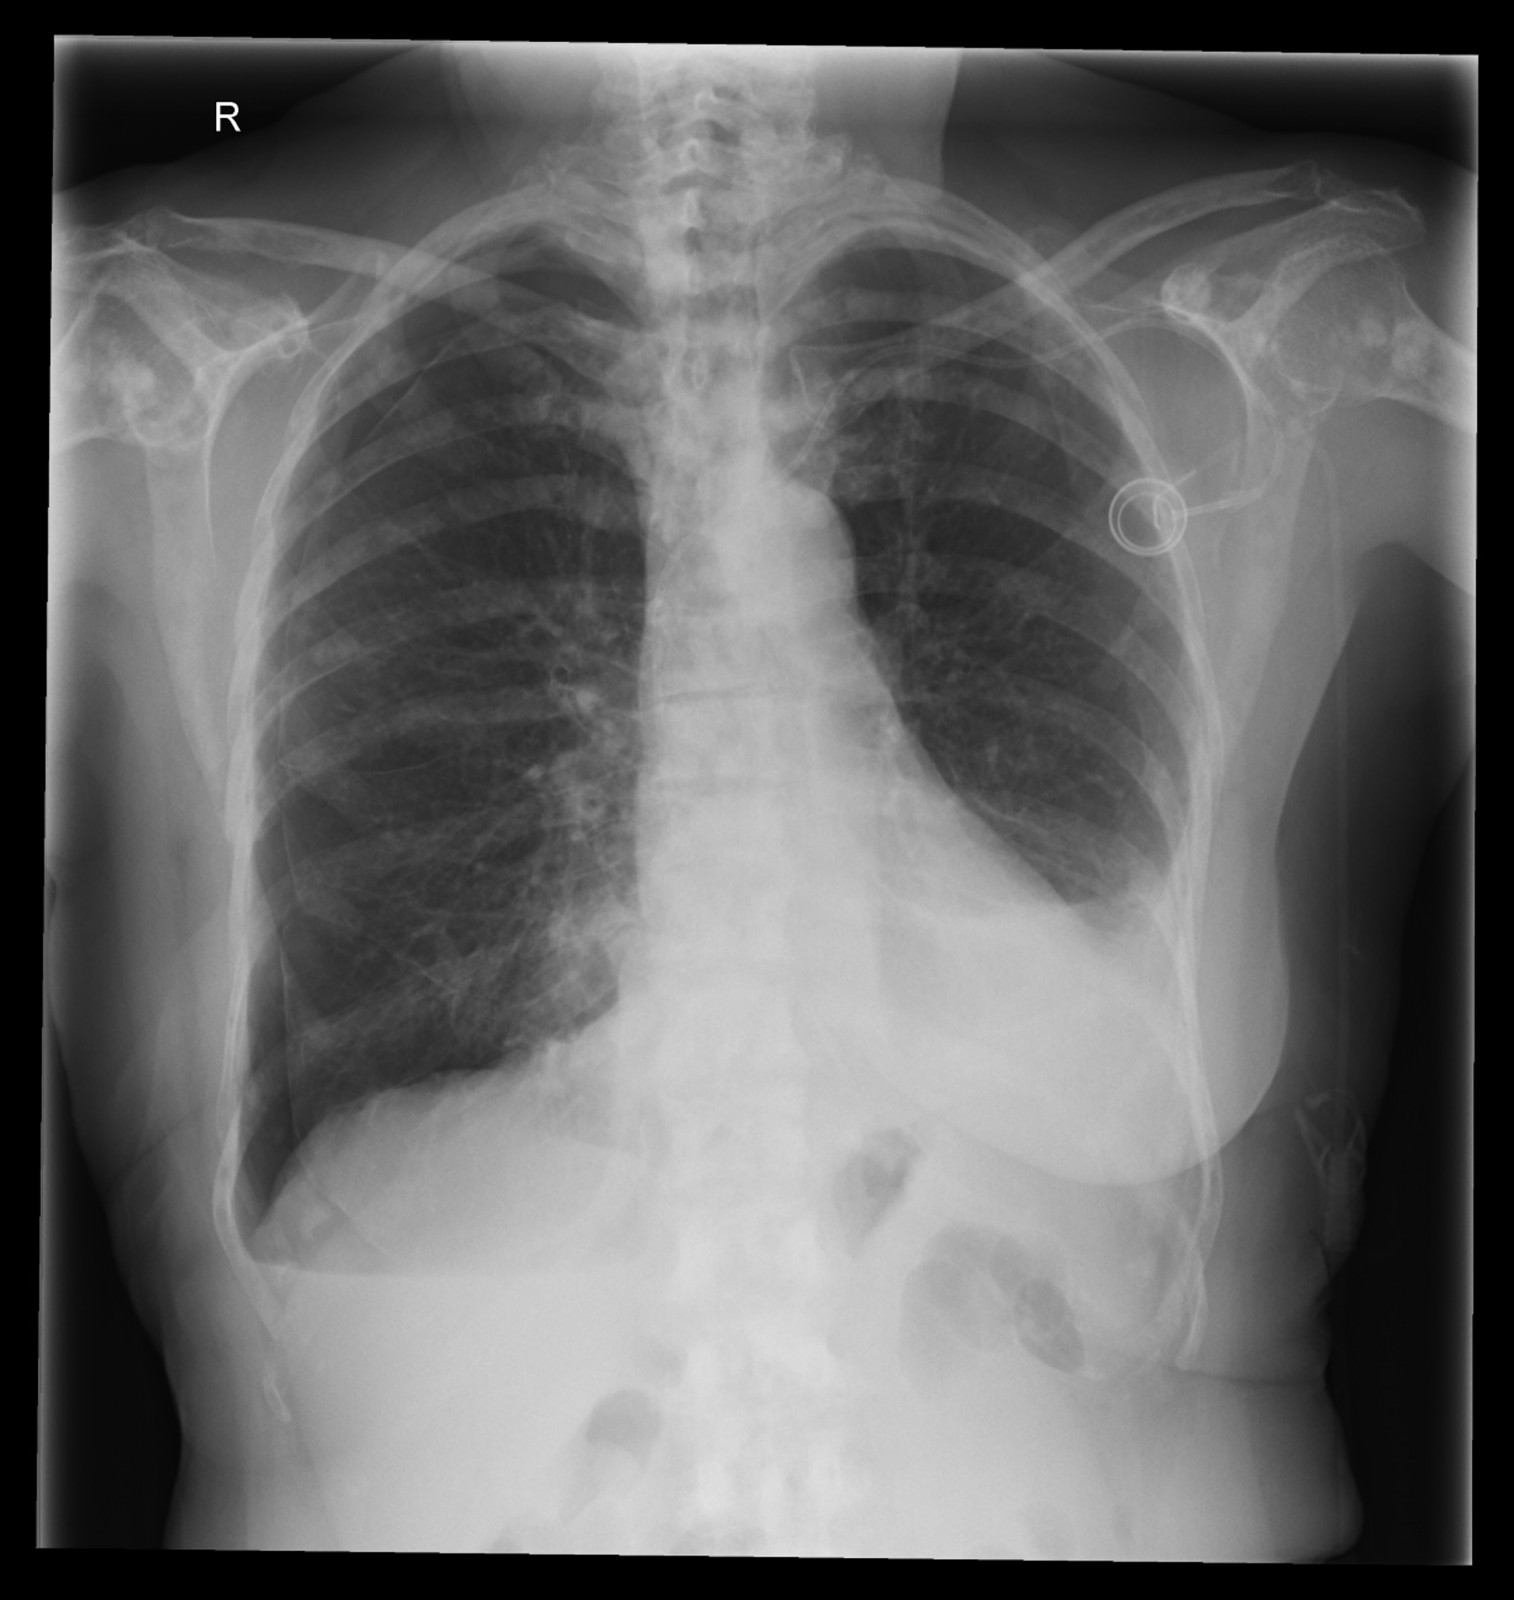

Röntgenfall des Monats Mai 2017 mit Auflösung

74 jährige Patientin mit diffusen Skelettschmerzen und akut aufgetretener Dyspnoe. Z.n. Mammakarzinom rechts.

ap

Bild vergrössern

seitlich